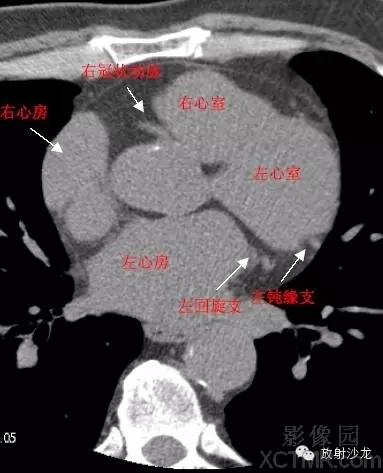

心脏冠状动脉CT解剖中文详细标注

LA -Left Atrium左心房

RA -Right Atrium右心房

LV -Left Ventricle左心室

RV -Right Ventricle右心室

LCX -Left Circumflex Artery左回旋支

LMB -Left Obtuse Marginal Branch 左边缘支(钝缘支)

RCA -Right Coronary Artery 右冠状动脉